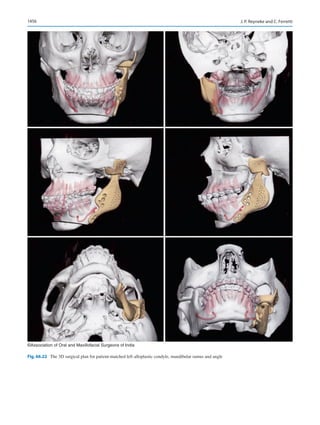

Diagnosis and Planning in Orthognathic Surgery������������������������������������������������� 1437

Johan P. Reyneke and Carlo Ferretti